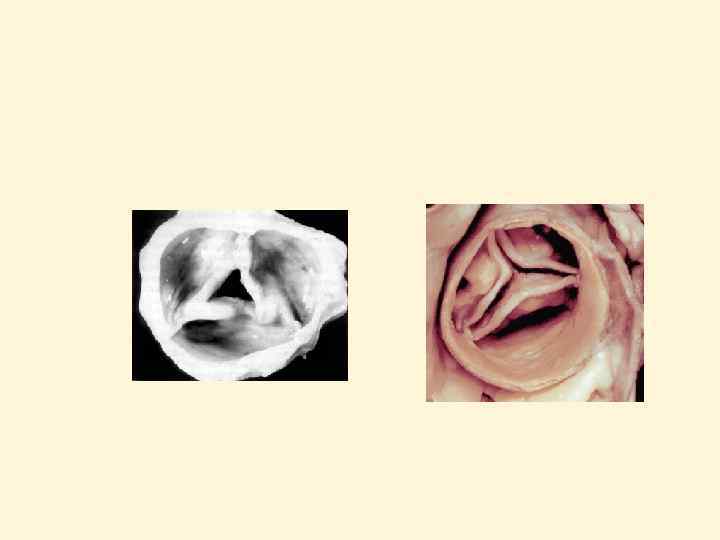

Характер поражения створок аортального клапана при различных причинах стеноза Норма 2 -ств. АК без кальциноза 2 -ств. АК с кальцинозом Стенозирующий кальциноз АК Ревматический стеноз АК

Сенильный дегенеративный кальциноз аортального клапана. Макропрепарат и УЗИ.

Двустворчатый АК. Макропрепараты и УЗИ. закрытие открытие